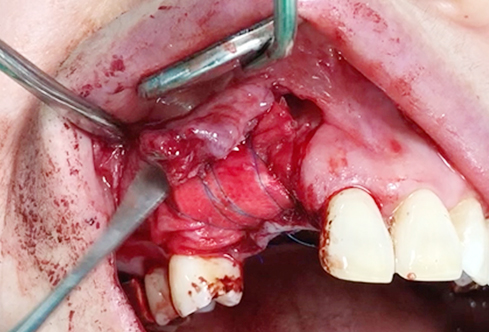

A surgical procedure using resorbable membrane

• A surgical procedure using resorbable membrane 1